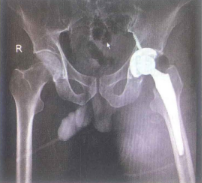

Hình 4.20. Hình ảnh X-quang sau mổ thay khớp háng (T) bán phần

1.2.4. Điều trị phẫu thuật thay khớp háng bán phần

Là phương pháp thay chỏm, cổ xương đùi bằng dụng cụ nhân tạo và giữ lại ổ cối tự nhiên.

Chỉ định:

- Người già >60 tuổi.

- Gãy cổ xương đùi, gãy sát chỏm, khớp giả cổ xương đùi.

- Bệnh nhân <60 tuổi nhưng tình trạng bệnh toàn thân nặng nề, cần rút ngắn thời gian phẫu thuật